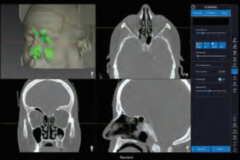

Navient ENT

NaviENT didesain agar tidak menghabiskan banyak menyita banyak tempat di sekitar meja operasi yang sudah sesak. Single Cart, ringkas, langsing, dapat dilipat, dan mudah didorong hingga ke dekat lokasi prosedur. NaviENT juga dengan mudah disimpan sesudah prosedur selesai.

Navient didesain fokus pada hal-hal esensial:

1.Mudah dan segera siap dipakai. SET UP CEPAT HANYA 5 MENIT

2.Akurat, akurasi hingga 0,2 mm

3.Biaya operasional yang sangat rendah. TIDAK MEMERLUKAN CONSUMABLE

4. Instrument dengan permanent marker yang dapat disteril. TIDAK DIPERLUKAN KALIBRASI INSTRUMEN SETIAP KALI PAKAI

5.Hemat ruang.